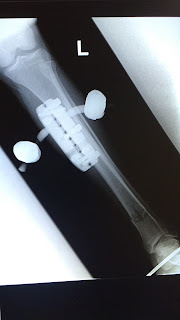

One surgery later, I was better in the sense that I was now partially a cyborg and also in excruciating pain.

I mean, I know I like Iron Man and all, but this is just ridiculous.

See below for a fun album of my bone being broken and then (sorta) fixed (well... stabilized, anyway) via an external fixator! (Warning: mild gore.)